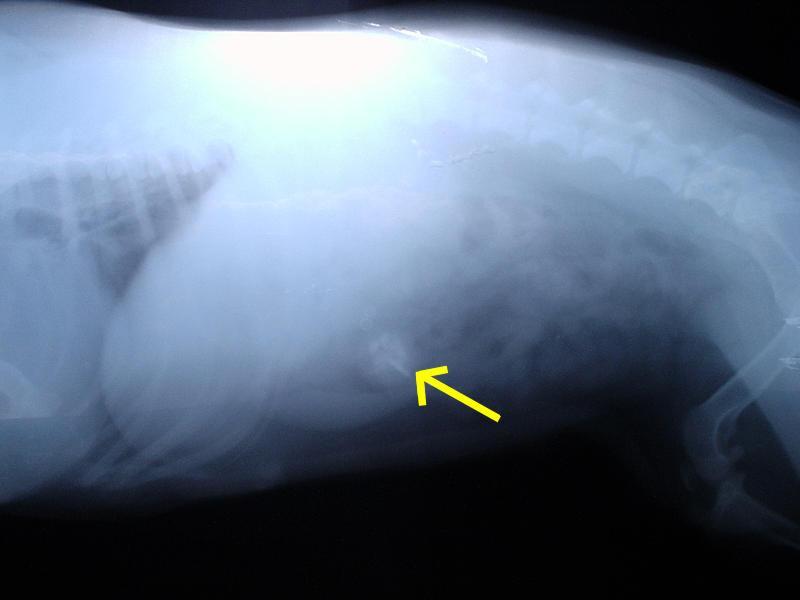

Foto galerie (fotky, obrazky): Cizí tělesa v zažívacím traktu a kostní trus.

Clanek: Cizí tělesa v zažívacím traktu a kostní trus.

Fotky: Cizí tělesa v zažívacím traktu a kostní trus. (foto, obrazky)